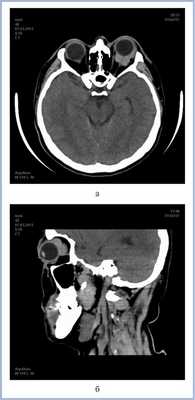

КТ глазницы с контрастированием. Правосторонняя лимфома вне конуса, образованного глазодвигательными мышцами, с поражением слезной железы.

а, b Двусторонние внутриглазничные лимфомы. На Т1 -взвешенном изображении очаги выглядят как гипоинтенсивные объемные образования (а) с выраженным усилением после введения гадолиния (b).

Мужчина 52 лет обратился в нашу клинику с жалобами на выстояние левого глаза и двоение в течение 2 мес. Проведен анализ клинической симптоматики. Инструментальные методы исследования включали флюоресцентную ангиографию (ФАГ) (Digital retinal Camera CX-1, «Canon», Япония), высокоразрешающее ультразвуковое дуплексное сканирование (УЗДС) (Voluson 730 Pro, «General Electric Healthcare», Австрия), компьютерную томографию (КТ). Диагноз верифицирован с помощью цитологического и гистологического (отделение патогистологии института, руководитель — проф. И.П. Хорошилова-Маслова) методов исследования.

КТ позволила выявить ретробульбарную ткань с достаточно четкими границами, локализующуюся вокруг зрительного нерва, а также утолщение хориоидеи слева (рис. 4). Патологических изменений справа по данным КТ выявлено не было. С помощью УЗДС слева в В-режиме непосредственно за задним полюсом глаза (вокруг зрительного нерва) определяли гипоэхогенную, практически однородную опухолевую ткань с четкими неровными контурами. Одновременно выявили диффузное утолщение хориоидального слоя в области заднего полюса глаза — до 2,5 мм (рис. 5, а). Ультразвуковой денситометрический анализ, проведенный на основе двумерных серошкальных гистограмм, продемонстрировал крайне низкие значения акустической плотности ткани (А=3—12 усл. ед.) (см. рис. 5, б). В режиме цветового допплеровского картирования (ЦДК) отмечена гиперваскуляризация ретробульбарного и интраокулярных очагов с высокими линейными характеристиками кровотока. Следует отметить, что два указанных процесса — внутриглазной и орбитальный имели единую васкуляризацию (см. рис. 5, в). Патологических изменений в правом глазу по данным ультразвукового исследования выявлено не было.

Рис. 4. Компьютерная томограмма орбит в аксиальной (а) и сагиттальной (б) проекциях.

Рис. 5. Результаты дуплексного сканирования. а — утолщение хориоидеи; б — денситометрические показатели акустической плотности опухоли в В-режиме; в — множественные собственные сосуды опухоли, единая васкуляризация внутриглазного и орбитального очагов в режиме ЦДК.

Данные клинического и комплексного инструментального обследования позволили предположить лимфому с одномоментным вовлечением глаза и орбиты слева и начальный процесс с правой стороны.